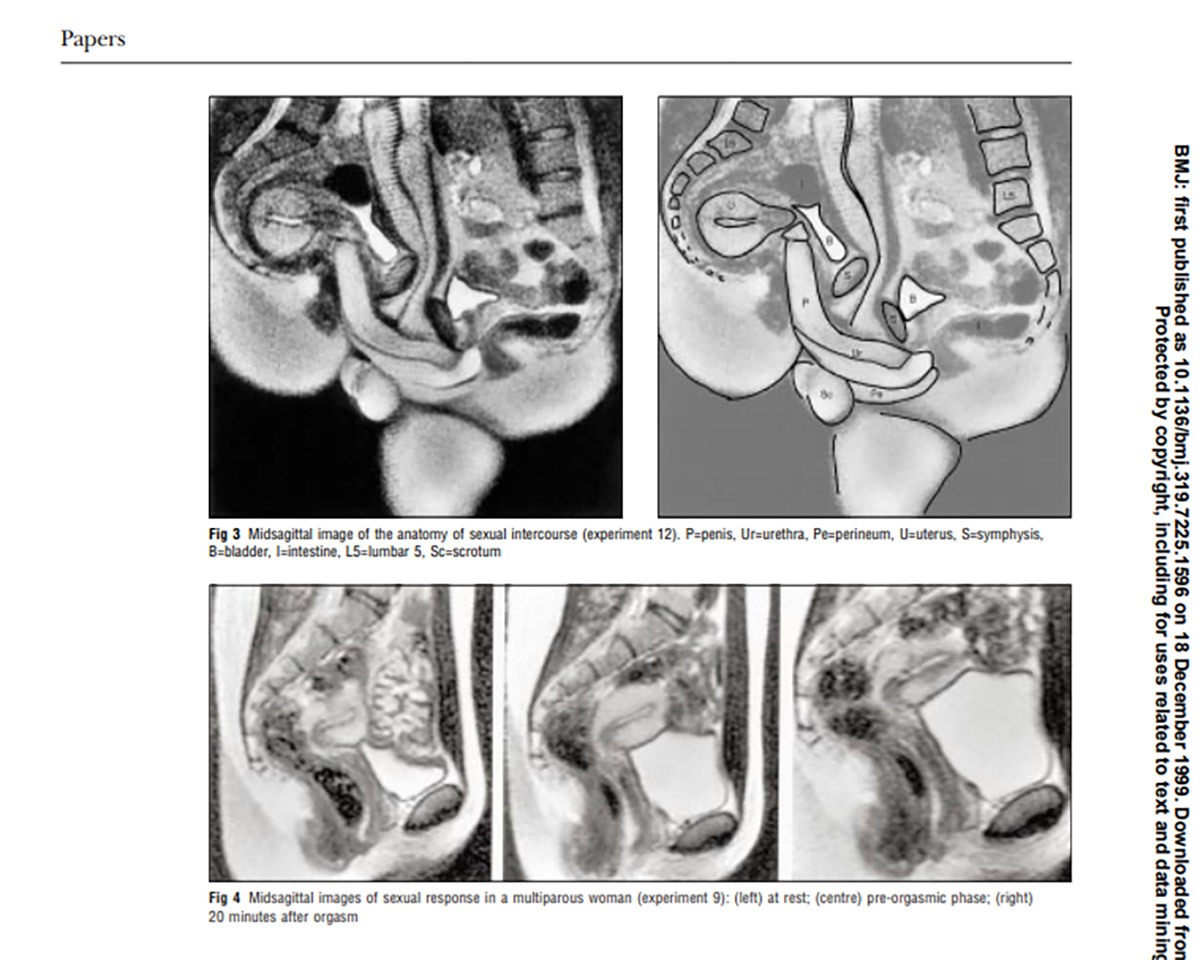

Ως προς το επιστημονικό σκέλος, η μελέτη του Van Andel απέδειξε εν τέλει ότι ο κολπικός σωλήνας σχηματίζει μια καμπύλη, σε μια εποχή που οι άνθρωποι δεν το γνώριζαν ακόμα αυτό. Mεγάλο μέρος της επιστημονικής κοινότητας είχε μείνει με τα σχέδια του Leonardo da Vinci από το 1492, σύμφωνα με τα οποία ο γυναικείος κόλπος έμοιαζε με έναν ευθύ κύλινδρο.

Οι εικόνες που ελήφθησαν έδειξαν ότι κατά τη διάρκεια της σεξουαλικής επαφής στην «ιεραποστολική στάση» το πέος έχει σχήμα μπούμερανγκ και το 1/3 του μήκους του αποτελείται από τη ρίζα του πέους. Κατά τη διάρκεια της γυναικείας σεξουαλικής διέγερσης χωρίς σεξουαλική επαφή, η μήτρα ανυψώνεται και το πρόσθιο κολπικό τοίχωμα επιμηκύνεται. Το μέγεθος της μήτρας δεν αυξάνεται κατά τη σεξουαλική διέγερση.

Με λίγα λόγια, οι επιστήμονες για πρώτη φορά διαπίστωσαν πως ο κόλπος δεν είναι ευθύς και πως το πέος μπορεί να λυγίσει προκειμένου να προσαρμοστεί στη φυσική καμπύλη του κόλπου κατά τη διάρκεια του σεξ.